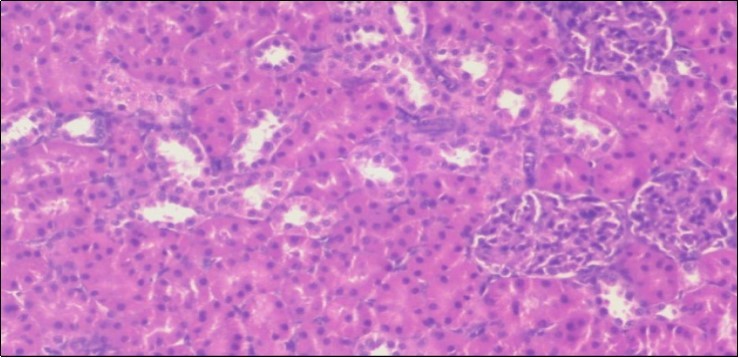

Effect of Ator, Fennel and Their Combination on the Liver of Obese Rats

The histological examination of the livers of control rats feeding standard diet showed normal architecture hepatocytes, blood sinusoid and central vein, figure 6. The rats which were fed on a (HFD), showed swollen hepatocytes with vacuolated cytoplasm filled with fatty infiltration, congested central vein and disappearance of blood sinusoids, figure 7. By comparison, the liver of rats that were treated by fennel after obesity and control mice observed nearly normal of the hepatocytes with eosinophilic cytoplasm, central vein and clear blood sinusoids and more bi-nucleated cells, figure 8. While examination of rats' liver that were treated by Ator and after the obesity appears, they showed mild fatty change in hepatocytes, few hepatocytes retain is eosinophilic cytoplasm and central vein figure 9. Liver of rats that were treated by fennel and Ator after obesity and control rats are showing nearly normal hepatocytes figure 10.

Figure 6.Photomicrogragh of liver section of control rat showing normal architecture Hepatocytes, blood sinusoid and central vein, (H&E) (40X).

Figure 7.Photomicrograph of liver section of obese rat showing swollen hepatocytes with vacuolated cytoplasm filled with fatty infiltration, congested central vein and disappearance of blood sinusoids, (H&E) (40X).

Figure 8.Photomicrograph of liver section of treated rat with fennel herb showing nearly normal of the hepatocytes with eosinophilic cytoplasm, central vein (CV) and clear blood sinusoids and more bi-nucleated cells , (H&E) (40X).

Figure 9.Photomicrogragh of liver section of treated rat with Ator drug showing mild fatty change in hepatocytes, few hepatocytes retain is eosinophilic cytoplasm and central vein , (H&E) (40X).

Figure 10.Photomicrograph of liver section of treated rat both with both fennel herb and Ator drug showing nearly normal hepatocytes (H&E) (40X).